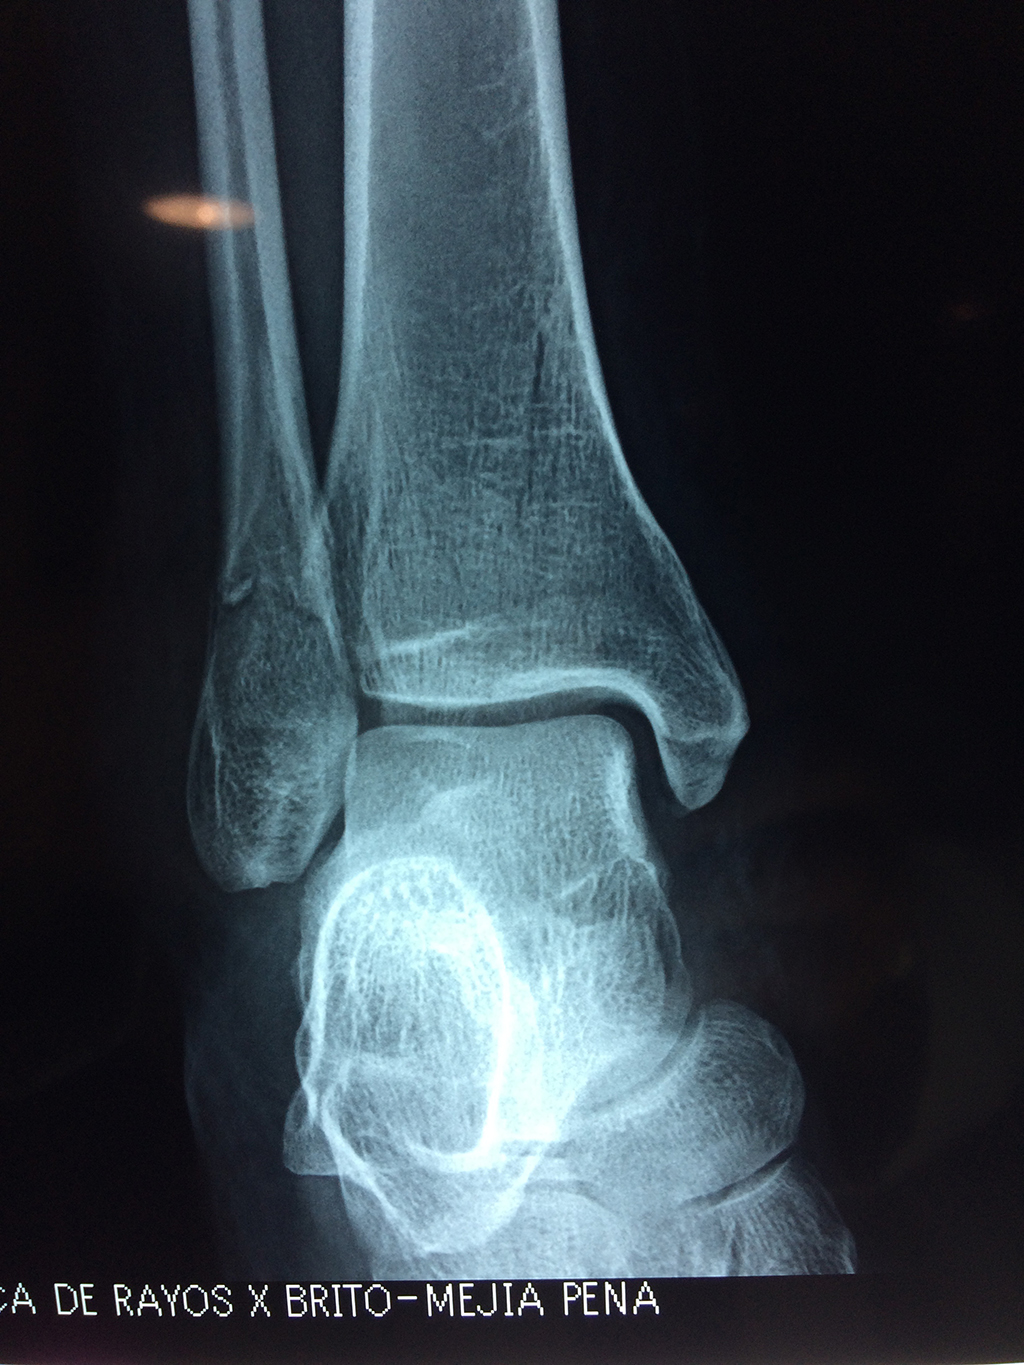

Una fractura de tobillo es la rotura de uno o más de los huesos del tobillo. Estas fracturas pueden ser:

- Parciales (el hueso está sólo parcialmente fisurado, no del todo).

- Completas (el hueso está perforado y está en 2 partes).

- Producirse en uno o ambos lados del tobillo.

Algunas fracturas de tobillo pueden requerir cirugía si:

- Los extremos de los huesos están desalineados entre sí (desplazados).

- La fractura se extiende hasta la articulación del tobillo (fractura intra-articular).

- Los tendones o ligamentos (tejidos que sujetan los músculos y los huesos entre sí) están rotos.

Cuando se necesita cirugía, es probable que esta implique el uso de clavijas de metal, tornillos o placas para sostener los huesos en su lugar mientras la fractura se consolida. Los elementos de soporte pueden ser temporales o permanentes.